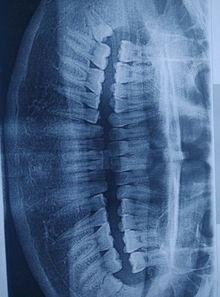

1. 智齿阻生:这张图片展示了一颗阻生智齿,可以看到它顶住了旁边的牙齿,导致牙龈红肿。